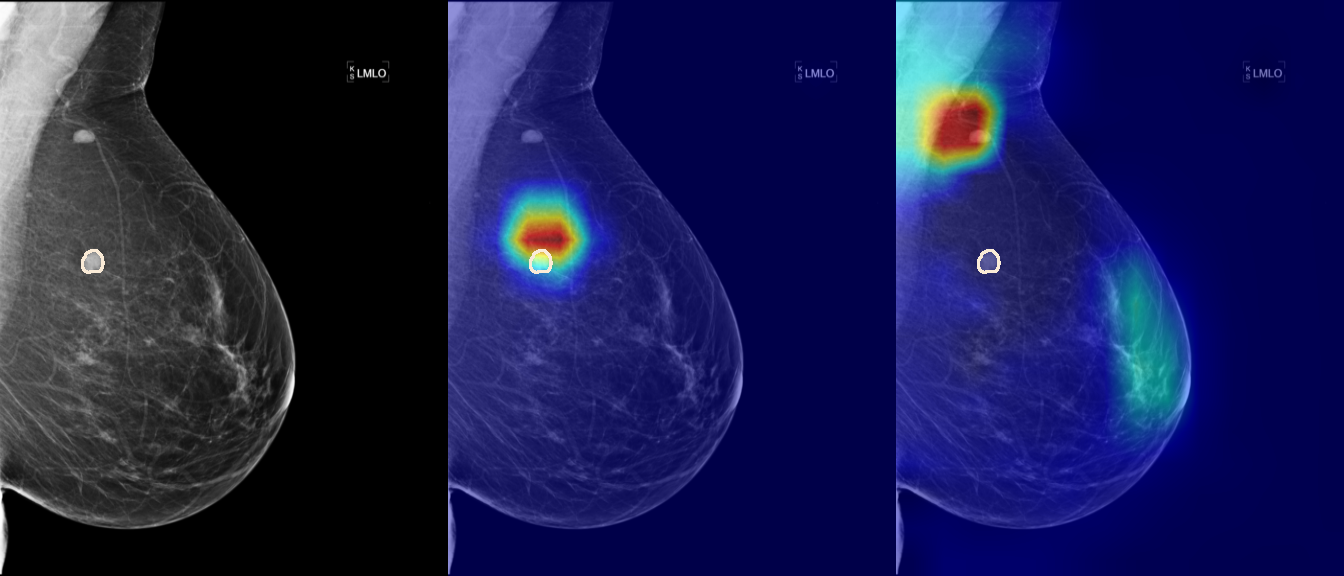

To interpret the decision-making process behind the quantitative results, we visualized Class Activation Maps (CAM) for the top-performing methods, ERM and VREx. Figures 1 through 2 illustrate discriminative regions identified by the models within the full mammograms.

Localization of Clinical Features: A key concern in medical AI is whether high performance stems from genuine pathology detection or spurious background correlations. Our visualizations suggest that Standard ERM achieves its superior quantitative performance by predominantly prioritizing clinical cues. As shown in the top rows of the Figure 1 and Figure 2, the ERM-trained models consistently focus attention on the specific lesion regions within the breast tissue. This demonstrates that despite lacking explicit invariance constraints, ERM is capable of learning robust, medically relevant features when trained on diverse multi-source data.

Attention Drift in Both Methods: While both ERM and VREx generally identify the correct region of interest in successful cases, neither method is immune to attention drift. We observe instances in both training paradigms where the model focuses on irrelevant areas, such as healthy fibroglandular tissue or background artifacts (e.g., rows 5 and 6 in Figure 1). This indicates that while VREx is designed to penalize instability, it does not guarantee perfect anatomical focus compared to the unconstrained ERM baseline.